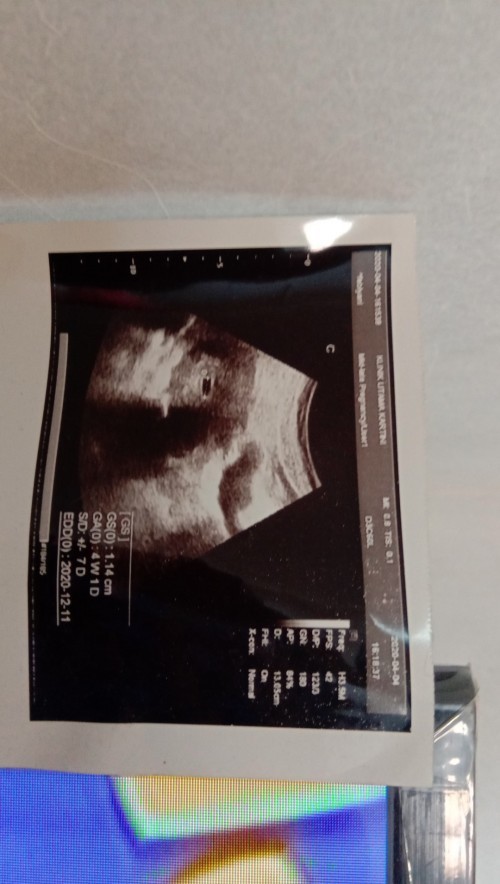

Usg kehamilan 4 mggu

masih kantong itu blm ada janin

saya baru kantungnya doang bun

5week mom, baru kantung

4 minggu bund

ini 4w bun